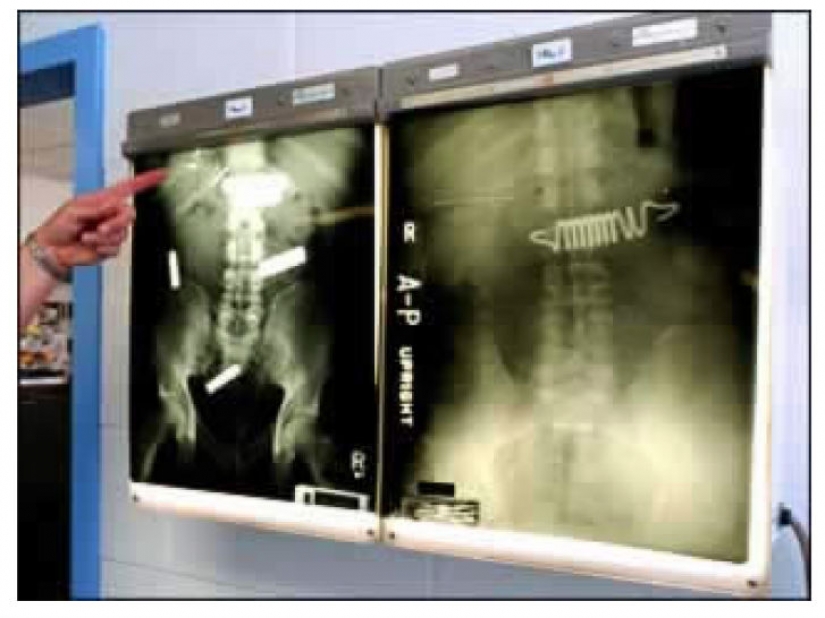

Algunos reclusos están dispuestos a tragarse cualquier cosa con tal de salir de la cárcel, por ejemplo, en el hospital, incluso los resortes del colchón.